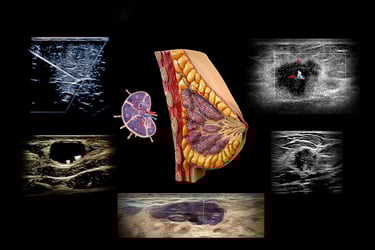

Every concept is explained in plain, practical language—anatomy, physics, instrumentation, Doppler, and pathology—so you always understand why you’re doing something before we show you how to do it. Then, nearly every minute is devoted to hands-on scanning with real-time, individual guidance that builds a repeatable breast imaging workflow you can trust in any clinical setting.

Breast imaging demands precision with sensitivity—clinical and interpersonal. This hands-on course matters because it teaches you to quietly detect subtle change and discern between benign and concerning patterns in a structured, guided setting.

You’ll refine image acquisition, Doppler assessment, and interpretation strategies that allow you to make confident clinical calls and communicate them effectively to patients and care teams.

Understand the “why” behind image and Doppler findings with easy-to-grasp physics explanations